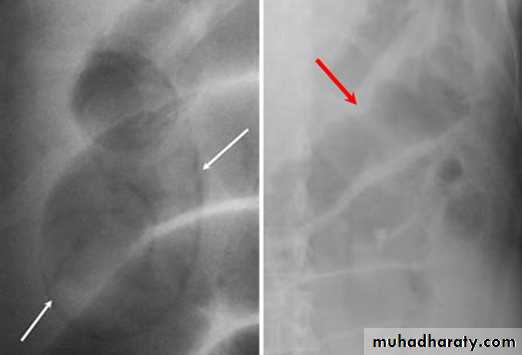

- upright films: dilated small bowel loops (>3 cm in diameter), air-fluid levels, and a paucity of air in the colon.

Small bowel obstruction

-The dilated bowel loops centrally located and lie transversely.-No/minimal gas is seen in the colon.

-valvulae conniventes,which completely pass across the width of the bowel

-ladder pattern

Multiple air fluid level, small and centrally located.

-Dilated loops of bowel

-periphery located.

-Larger bowel diameter

-Huastration (incomplete line)

-longer length airfuid level , less in number

Large bowel obstruction